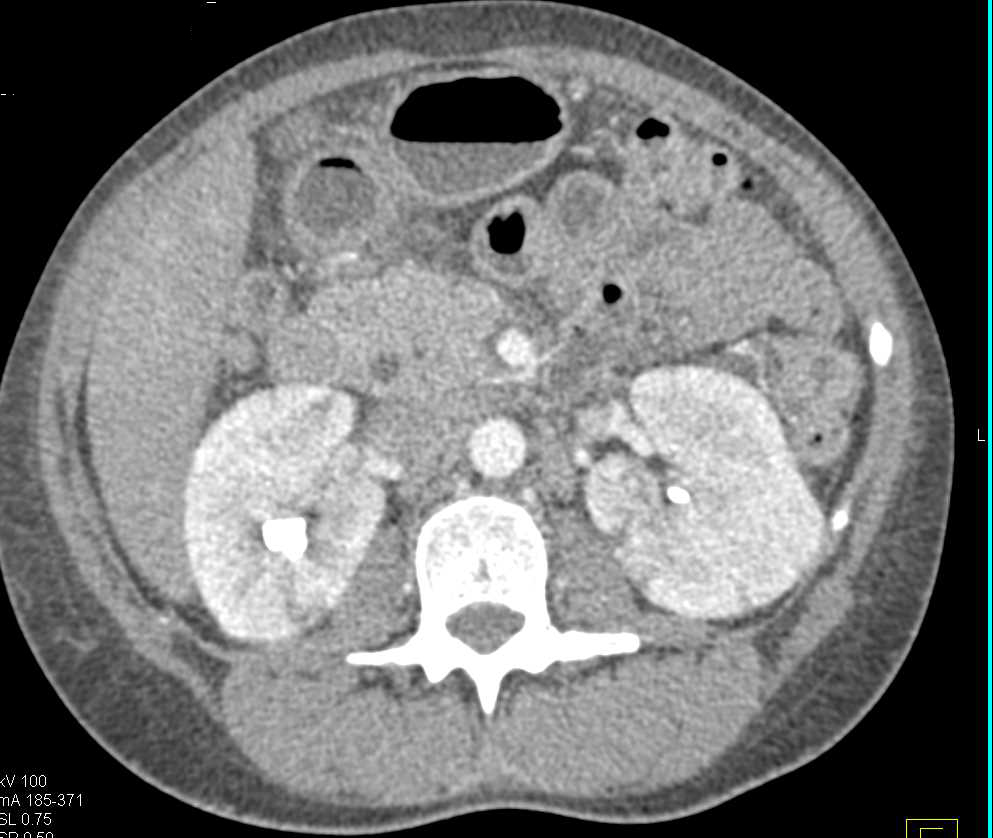

Horseshoe Kidneys with Infarcts